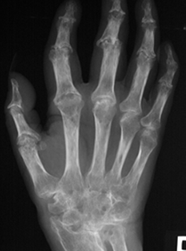

Las erosiones se aprecian como áreas radiolúcidas, relacionadas con los sitios de inserción de los ligamentos interóseos y la sinovial. Los lugares con cambios más tempranos son la base del 3º y 4 º metacarpianos, entre los huesos grande y ganchoso y el lado ulnar del ganchoso. (6). (Fig 21 y 22).

Fig 21. Artropatía reumática.

A: Rx AP de mano. Hallazgo precoz de la enfermedad, con erosión marginal.

B: Estado mas avanzado con varias erosiones en los metacarpianos y las falanges.